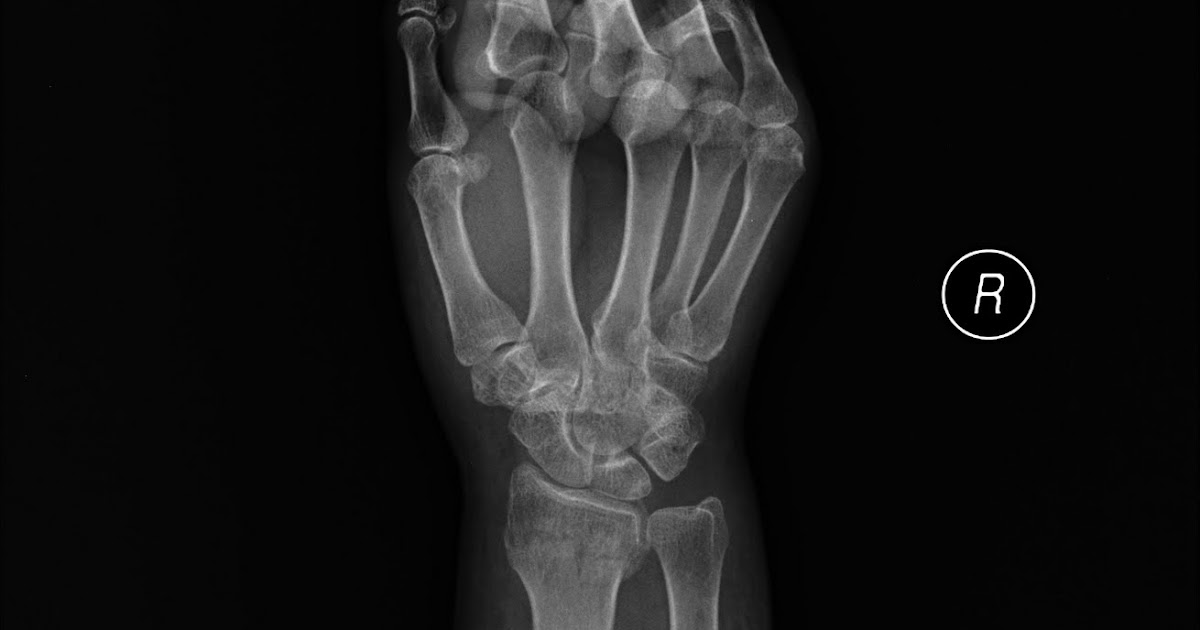

The ulna bone may also be broken. May involve articular surface frequently involving the ulnar styloid most often result from a 10: Management of distal radius fractures. These fractures have varied patterns, so a single form of treatment usually does not apply. Fracture at the metaphysis or the articulation of the distal radius. The ulna bone may also be broken. Distal radius fracture clinical practice guideline. Distal radius fractures are a predictor of subsequent fractures. Acute median and/or ulnar nerve damage (~10% of low. A distal radius fracture is a common bone fracture of the radius in the forearm. Apparent volar tilt of the surface of the distal radius, as measured on the lateral view, increases with supination and decreases with pronation of the wrist (5). The 7th character should be used when the patient. A distal radius fracture, also known as wrist fracture, is a break of the part of the radius bone which is close to the wrist. Falls are the main cause of distal radius fractures. Related online courses on physioplus. One of the most common fractures seen in the ed (1/6th of all fractures treated). Distal radius fractures occur through the distal metaphysis of the radius.